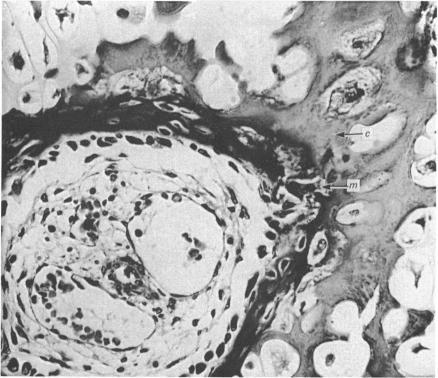

Bone formation in the vertebral centra commences within the centrum and is in this respect analogous to the secondary ossification which occurs in the epiphysis of a long bone. Bone tissue first appears at about the 85 mm C.R. stage and not in the 55 mm C.R. length embryo; at the latter stage blood vessels and calcification alone were observed. The connective tissue cells within the cartilage canal appear to assist osteogenesis by providing osteogenic cells which lay down bone in the walls of the cartilage canal, and provide cells which remove calcified cartilage found at the periphery of the canal; they assist growth by producing an appreciable number of chondrocytes that permit lateral expansion of the centra. Osteogenesis appears to occur in multiple foci within the growth plate of the older embryos and could account for the rapid rate of growth of vertebrae. Bone formation occurs in both mineralised and unmineralised matrix (as seen on the walls of the cartilage canals). The blood vessels within the growing vertebra tend to follow the zone of cartilage hypertrophy.